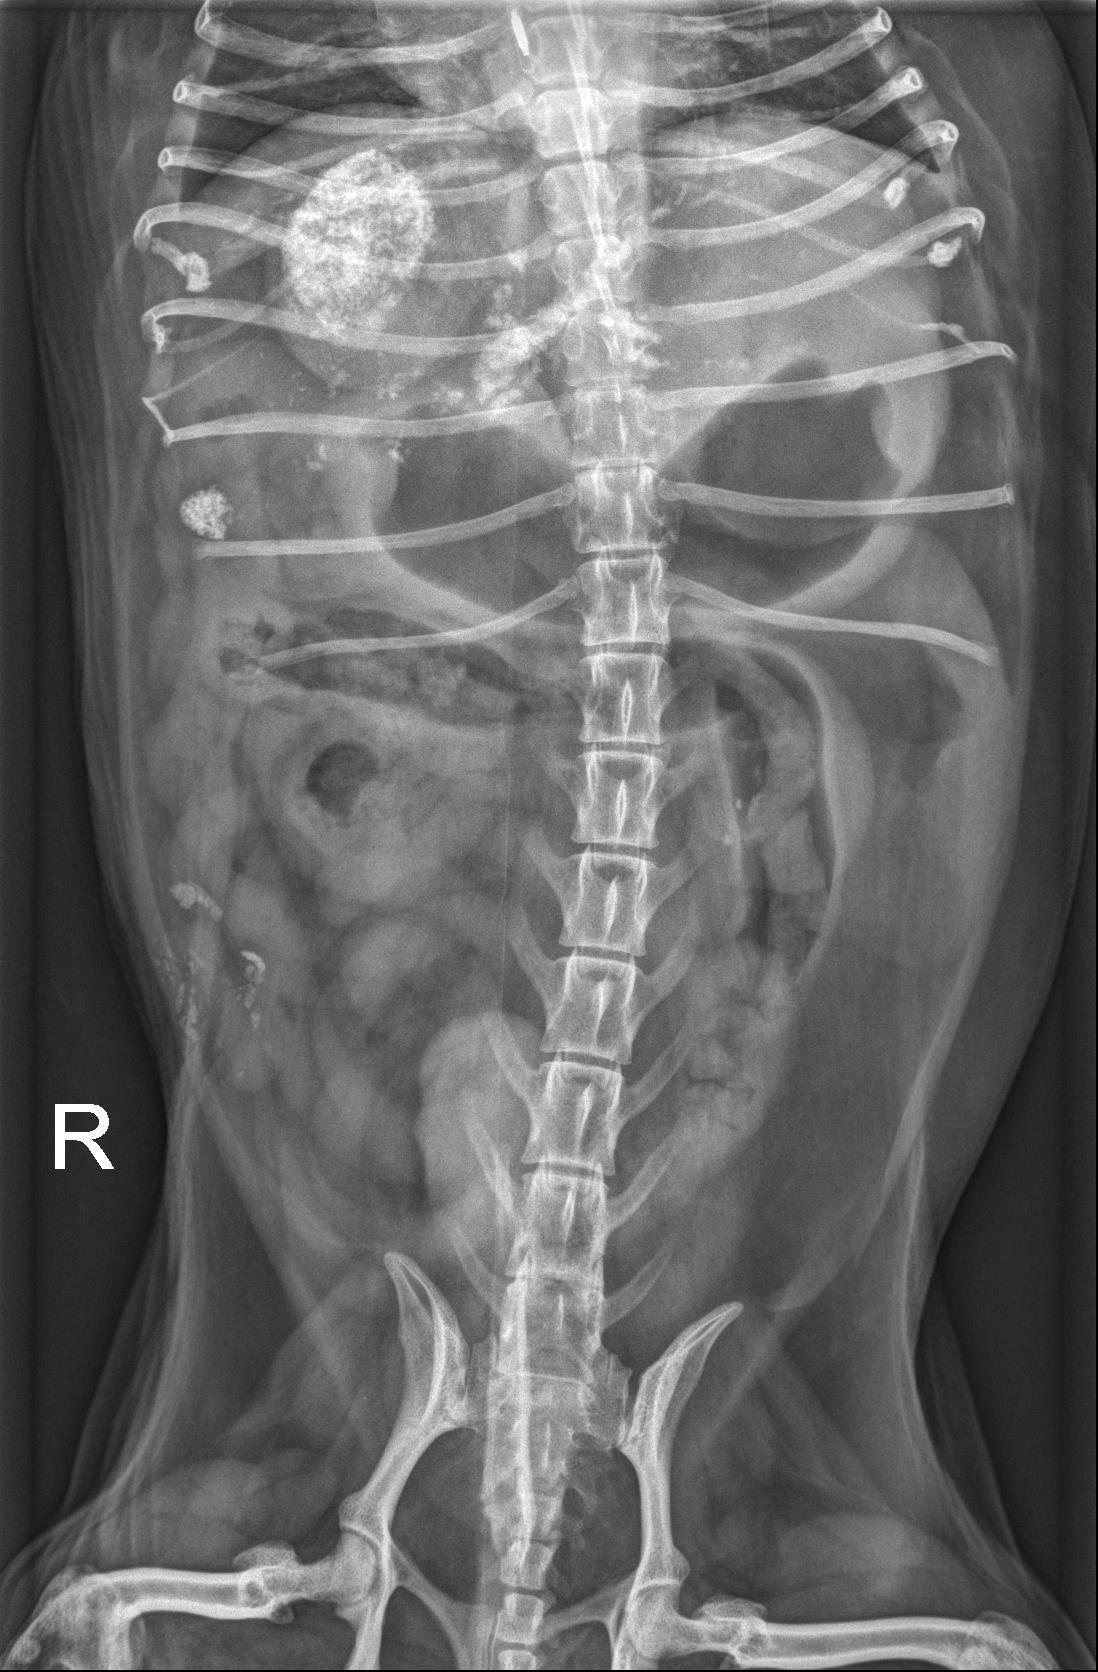

Abdomen - ventrodorsal and lateral radiographs are available for interpretation.

Abdominal serosal detail is normal.

There are numerous, stippled to angular, mineral opaque foci in the gallbladder and throughout the hepatic parenchyma which are suspected to be within the biliary tract, given the linear/arborized appearance. The liver is mildly enlarged with rounded margins extending beyond the costal arch. Best identified on the ventrodorsal radiograph, there is focal accumulation of this mineral superimposed with the proximal portion of the descending duodenum.

The stomach contains a small to moderate volume of gas and homogeneously soft tissue/fluid opaque material. The small intestines contain a small volume of homogeneously soft tissue/fluid opaque material and scant volumes of gas. The colon contains a small volume of heterogeneous fecal material and gas.

The kidneys have mildly undulant margins and contain multiple punctate to linear mineral opacities. There are numerous, small, well-marginated, round, faintly mineral opaque foci within the urinary bladder. The spleen is normal.

There is a small volume of mineral opaque material superimposed with multiple small intestinal segments on the ventrodorsal radiograph. On the lateral radiograph, this material is present superimposed with the retroperitoneal space at the level of the fourth lumbar vertebra.

Severe cholelithiasis and choledocholithiasis with suspected accumulation of mineral opaque material at the level of the duodenal papilla likely resulting in at least partial obstruction, given the reported clinical signs and labwork abnormalities. The planned abdominal ultrasound is recommended for further evaluation.

- Moderate hepatomegaly is non-specific, but likely represents a benign processes such as vacuolar degeneration or nodular hyperplasia. Malignancy (such as infiltrative round cell neoplasia) is considered less likely.

- Bilateral chronic renal degenerative changes and nephrolithiasis. Cystolithasis.

– The appearance of the gastrointestinal tract is most consistent with a non-specific gastroenteritis, given the reported vomiting.

– The mineral opaque material superimposed with the right caudal abdomen at the level of the fourth lumbar vertebra is suspected to represent mineralization of the extra-abdominal soft tissues.